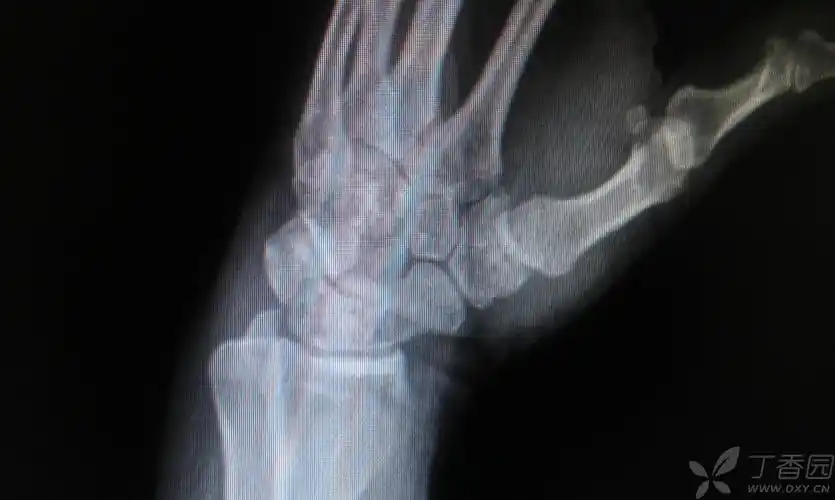

第一掌腕关节畸形